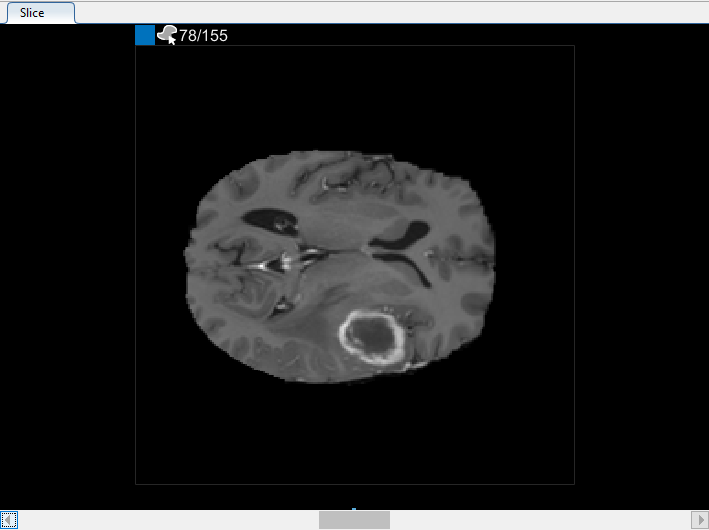

Можно также просмотреть каждый срез объема в панели Среза. Используйте ползунок в нижней части панели, чтобы переместиться от среза до среза. Вы видите опухоль на срезе 35 через срез 88. По умолчанию панель Среза отображает объем, ориентированный вдоль оси X-Y, но можно изменить это использование кнопки в разделе Orientation панели инструментов на вкладке Segmenter. Панель Среза также, где вы используете инструменты для рисования, чтобы задать маску.

После использования интерполяции проверяйте отдельные срезы, чтобы видеть, создала ли интерполяция удовлетворительные ROI. Обратите внимание на то, что ROI на срезе 71 не заполняет целый объект, который вы хотите сегментировать. Можно вручную настроить ROI с помощью инструмента Paint Brush. В качестве альтернативы можно использовать один из инструментов на вкладке Automate. Например, можно использовать Активные Контуры, чтобы вырастить ROI на срезах, где это не заполняет полный размер опухоли.

В панели Среза перейдите к срезу, где объект сначала появляется, и начните помечать объект на каждом срезе с помощью инструмента для рисования. В следующем рисунке этот пример использует инструмент Paint Brush, чтобы пометить опухоль. Как ранее, можно чертить объект на каждом срезе, где это появляется, или используйте инструменты интерполяции, чтобы привлечь несколько срезов автоматически. После интерполяции можно использовать инструменты для рисования, такие как Средство стирания, чтобы изменить автоматизированную сегментацию на каждом срезе.